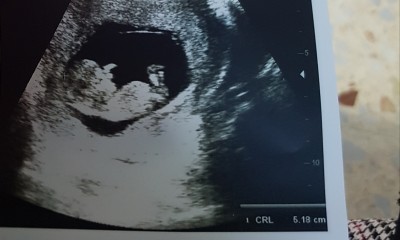

Cinsiyet tahmini alabilirmiyim:) 12+1

Sizceeee:)

Gebelik haftası

12+1

Tam belli olmuyor ama kızdır sanki siz öğrendiniz mi bende iki gün sonra tam 12 haftami dolduruyorum hastaneye gitsem söylerler mi cinsiyetini

12 ila 14 . Hafta arasında cinsiyet yerleri oluşuyor o yüzden ne desek boş net olarak 14. Haftada belli olur

Bence erkek Bebek

Kesesine göre erkek gibi ama Allahu âlem :)